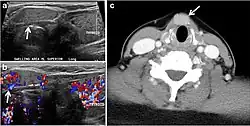

Fig. 4. A 45-year-old male patient presented with anterior mediastinal metastatic PTC lesions and occult primary on imaging. Histopathology examination of the resected thyroid gland revealed micro-foci of PTC; the largest, in the isthmus, measured 4 mm. a transverse greyscale ultrasound of the thyroid demonstrates homogeneous gland with normal echogenicity and size. No focal lesion or micro-calcifications. b Non-enhanced CT scan obtained as part of PET/CT examination shows a heterogeneous, large, relatively dense anterior mediastinal mass (white arrow) with peripheral calcification (arrowheads). Thyroid gland has normal CT appearance with no abnormal FDG uptake (not shown).[1] -